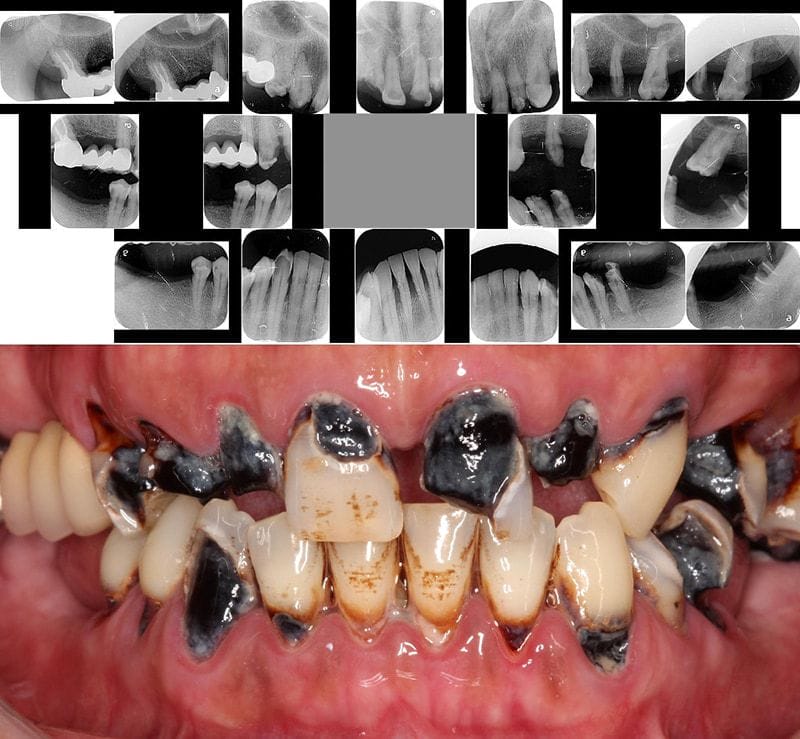

案例中是一位四十多歲的先生,他除了全口有中等到嚴重程度牙周病以外,也有嚴重的蛀牙齲齒及缺牙造成全口咬合崩壞。

在來桃園當代牙醫找我之前,他也去了其他院所評估過,不少醫師提供的方案是『一日全口重建』或是『All-on-4全口重建植牙』,優點是會讓患者比較快有假牙,但缺點是可能要犧牲拔除很多顆牙齒。(幸運的是,他跑來找我~ 牙齒命不該絕~~)

我檢查評估後,我認爲經過牙周病的治療後,他大部分現有的牙齒可以治療保存,但是需要比較長的時間。

即便是這麼嚴重的牙周病跟蛀牙、咬合崩壞,只要一個念頭,患者願意下定決心,就還來得及。我們先從牙周病第一階段療程開始,這個時期除了治療嚴重牙周病,也要養成患者願意配合,把口腔衛教習慣做好。(這才是根本~~ 又強調了一次)

積極治療保留每一顆牙齒,包括多顆根管治療、全瓷貼片與全瓷牙冠、上顎植牙一顆與下顎植牙四顆。

一年多的時間完成所有的治療,扣除一顆智齒斷根以外,治療這麼嚴重的牙周病沒有拔牙。

非常感謝患者的耐心與信任(這點很重要),完成後他能夠放心地吃東西,也能自信開懷展露笑容,對我來說真的是最棒也最有成就感的回饋!看他術後開心活潑的樣子,我寫這文章整理照片時,看了也很開心呢!